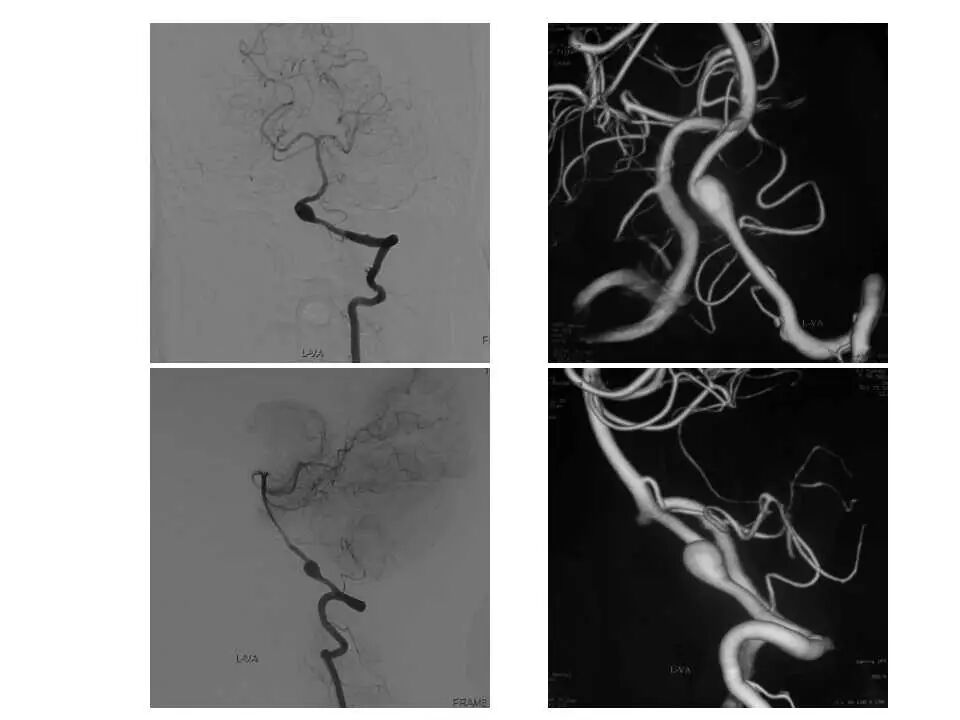

今天为大家分享的是“强生医疗CNV-神经介入专栏”第十五期,由首都医科大学宣武医院何川教授带来的“颅内动脉瘤介入治疗”精彩讲课视频及PPT,欢迎观看、阅读。文章仅代表作者个人观点,如有不同见解,欢迎同道斧正!

何川 ,首都医科大学宣武医院副主任医师,中国医师协会神经介入专业委员会常务委员,长期从事脑血管病和脊髓血管病的手术及介入治疗和相关研究工作。首都医科大学神经外科博士,师从于中国神经介入开创人凌锋教授;日本东北大学医院脑血管病治疗科博士后,师从于日本国脑血管病血管内治疗的开创者高桥教授。